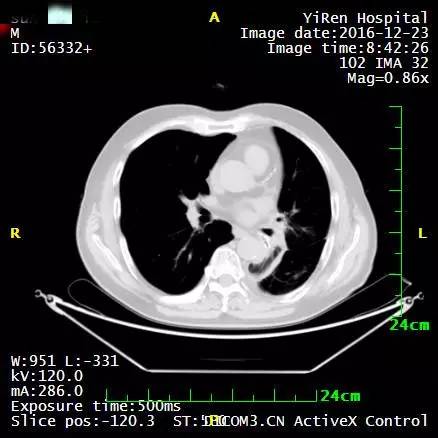

2、患者男性,64岁,小细胞肺癌

2016年3月,王先生因咳嗽加重就诊于当地医院,支气管镜病理检查提示:考虑小细胞癌的可能性大。

化疗一周期,病情无改善症状加重。

2016年4月,王先生接受了A45治疗,一个月后复查,病灶明显缩小,2016年7月复查,病灶进一步缩小,由于A45治疗具有明显的远观效应,能够激发自身的免疫系统,长期有效的消灭体内肿瘤,2016年12月,王先生肺部病灶几乎全部消失。

治疗前

治疗后

治疗后两个月

治疗后7个月

目前王先生态势良好,没有任何复发迹象。